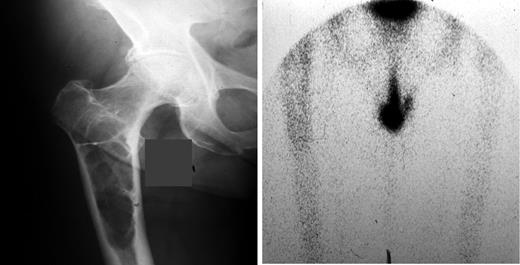

Technetium-99m bone scanning is not appropriate for evaluating myeloma bone disease since bone scans reflect osteoblastic activity and, thus, underestimate the extent of osteolytic lesions characteristic of myeloma bone disease (Figure 1 ). Technetium-99-sestamibi scanning has been investigated in myeloma patients because it is concentrated in myeloma tissues. In a multicenter study of 397 whole-body scans compared to standard radiography, sestamibi scanning was found to be more sensitive than radiographs (77% vs 45%) and was highly specific for staging myeloma patients.7 These results suggest that sestamibi scanning could be useful for staging myeloma.

Bone scans can underestimate the degree of bone involvement in myeloma because bone disease in myeloma is characterized by bone destruction with absent new bone formation. This patient has a large lytic lesion on plain radiographs and a negative bone scan. Courtesy of Dr. Mankin, Massachusetts General Hospital.